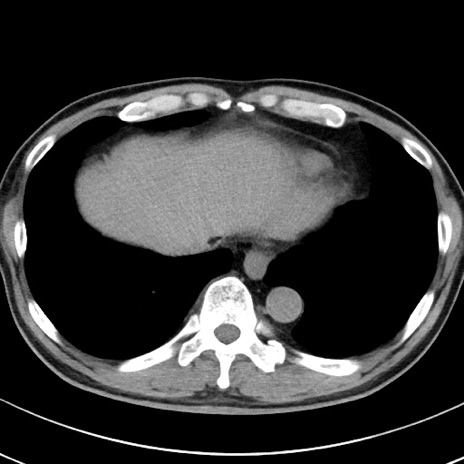

【腹部TIPS】症例29 参考症例 CT(横断像)

症例

70歳代男性